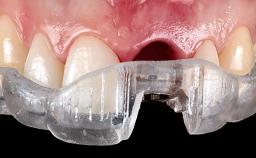

This case describes both a surgical and an anti-infective approach for the management of peri-implantitis, including treatment of the entire dentition to eliminate any deep periodontal pockets that could serve as reservoirs for bacterial re-colonization at the implant site. A 65-year-old female patient was referred to the periodontist in 2013 for assessment and management of an infection at implant 12. On examination, probing depths at implant 12 were 11 mm with suppuration and bleeding on probing.